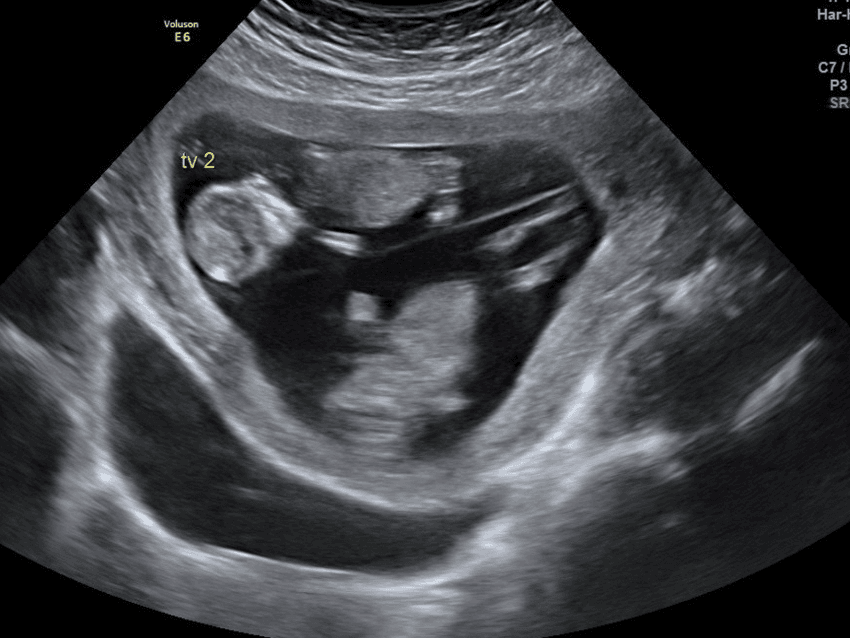

Tvillinggraviditet

Tvillinggraviditeter skiljer sig från varandra, där vissa är mer komplicerade än andra. Via ultraljud konstateras vilken typ av tvillinggraviditet som väntas och utifrån det läggs en plan för den resterande graviditeten upp. Det ser olika ut i landet, men ofta innebär det fler besök hos mödravården, vissa går varje vecka och andra varannan. Det kan även bli aktuellt att graviditeten följs upp hos specialistmödravården som ofta ligger i anslutning till sjukhus. På besöken träffar man barnmorska, läkare och ultraljudsenheten. Tillsammans med läkare planeras den kommande födseln och detta skiljer sig från en singelgraviditet då en planering endast sker i enstaka fall om det bara är ett barn i magen – medan den då planeras vid varje fall inför en tvillinggraviditet. Vid flera tillfällen under graviditeten kontrolleras tvillingarna med hjälp av ultraljud och vid en singelgraviditet erbjuds oftast bara två ultraljud om inget avviker.